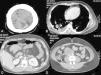

Presentación de casosCaso 1Masculino de 24 años de edad, con antecedente de resección de tumor testicular un año antes, y que no aceptó tratamiento posterior. Ingresó al Servicio de Urgencias por evento de hemorragia de tubo digestivo bajo, manifestado por hematoquezia de 2 días de evolución. A la exploración física se encontró hipotenso, taquicárdico y con hematoquezia de 500mL. Fue realizada una colonoscopia y panendoscopia que no demostraron lesiones. Por tomografía se demostró tumor retroperitoneal compatible con actividad tumoral, así como imágenes sugestivas de metástasis pulmonares y renales (fig. 1). Fue realizada arteriografía que demostró hemorragia activa a nivel de yeyuno (fig. 2A). Fue sometido a resección intestinal con anastomosis primaria. Desde el postoperatorio inmediato presentó deterioro neurológico, por lo cual se realizó tomografía de cráneo que evidenció metástasis cerebrales. El paciente falleció al cuarto día postoperatorio. El reporte definitivo fue metástasis hemorrágicas de coriocarcinoma en yeyuno (fig. 2B).